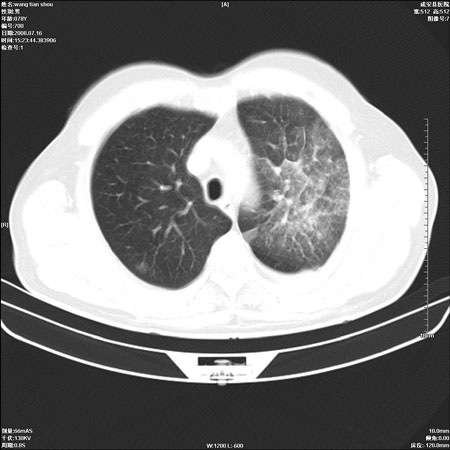

以下是引用qingjing在2008-7-16 19:55:00的发言:[br]1、左上肺不张并堵塞性炎症,建议支气管镜详查;[br]2、左侧胸腔少量积液。

以下是引用wzr在2008-7-16 20:26:00的发言:[br]左肺肺不张伴阻塞性肺炎!另:左侧胸腔少量积液。建议纤支镜检查!